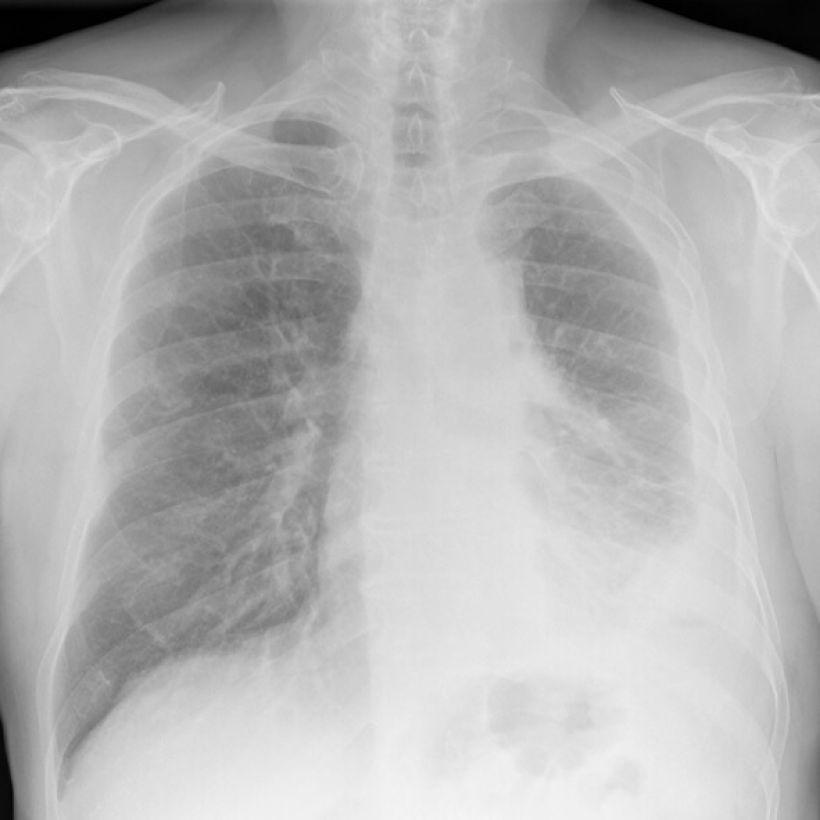

X-rays are mesothelioma imaging scans that offer a fast, low-dose way to look for problems in the chest. Doctors use them to spot fluid around the lungs, areas of unusual thickening or a collapsed lung that may signal pleural disease.

On the image, bone looks white, air looks black and fluid or thick tissue looks gray.

Doctors check for warning signs linked to mesothelioma, like pleural effusion, pleural thickening, or a partly collapsed lung. X-rays can miss small or early tumors, and they do not diagnose cancer alone. If your X-ray raises concern, your doctor will order advanced scans and, if needed, a biopsy to be sure.

What Does Mesothelioma Look Like on an X-Ray?

On a chest X-ray, pleural or pericardial mesothelioma tumors appear as wispy white areas around the lungs, while calcified tumors appear bright white. Bones appear white and healthy lungs are dark. Most abnormalities appear as lighter areas that are hazy or solid.

Tumors and scarring may distort chest anatomy. Compressed lungs or a raised diaphragm can be visible on an X-ray.

X-rays are 2D, making it hard to determine if a tumor is in the lung, pleura or the mediastinum around the heart. Additionally, X-rays don’t clearly show peritoneal or testicular mesothelioma. CT, MRI and PET/CT scans offer more detailed images for all mesothelioma types.